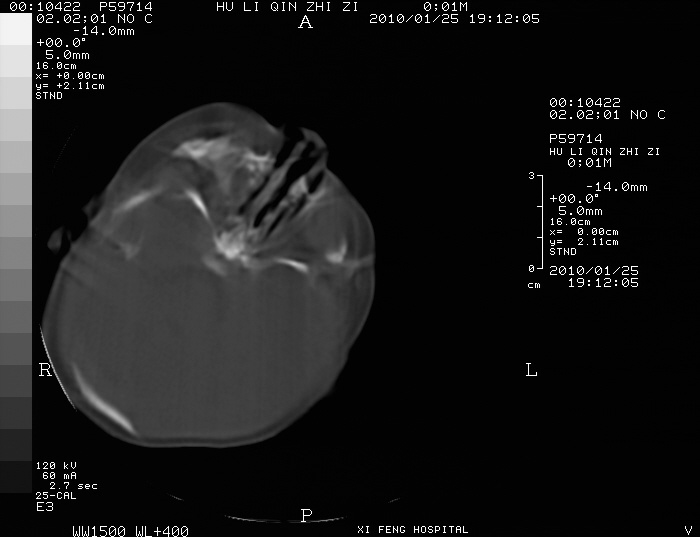

男  新生儿,曾做b超股骨长5.5厘米,疑畸形,家族中有多个身才矮小.曾孕两次,一次流产,一次宫内死亡

谢谢,我也考虑,颅骨有问题吗?仅仅是颅缝增宽还是还有骨化差。

如果颅骨有骨化差,那就不应该考虑软骨发育不全了,

四肢干骺端呈喇叭口型缺损,颅骨缝增宽,支持软骨发育不全。